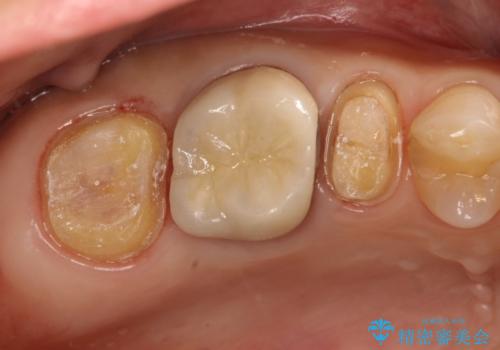

虫歯もしっかり除去して、適合の良い補綴物を装着しました。